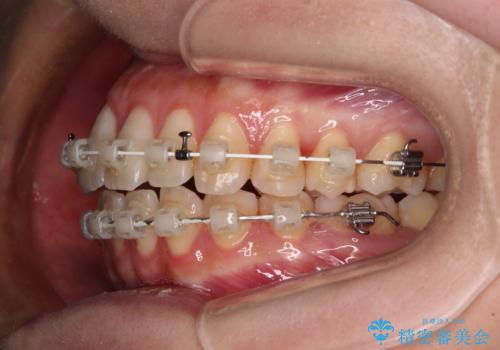

- 審美装置

- 3年

- 10-30回

1年弱で治療方針を変更したため、治療期間は長くなりましたが、スペースは無事に閉じ、咬合の違和感なく仕上げることができました。